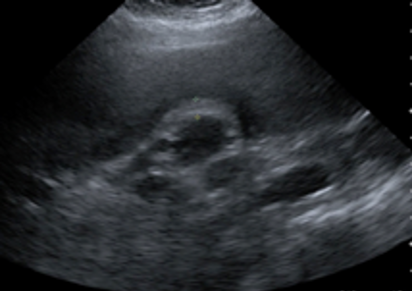

Abdominal ultrasonography (Figures 1 and 2) showed the gallbladder to be abnormal and completely filled with stones. The gallbladder wall was thickened, measuring up to 7 mm—a finding consistent with acute calculous cholecystitis. No definite fluid was seen in the gallbladder fossa, and no dilated common bile duct was noted.

Figure 2. Abdominal ultrasonography showing gallbladder wall thickening.